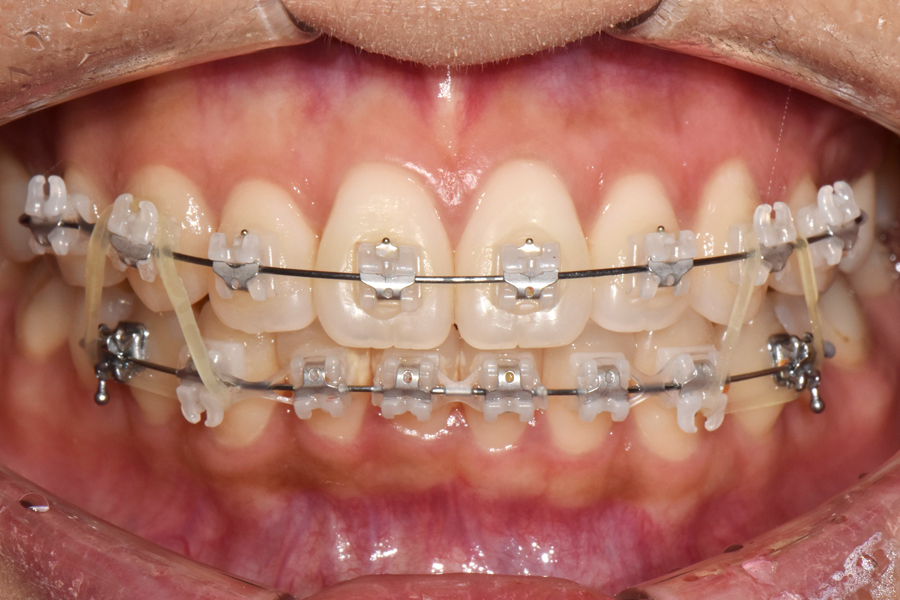

초창기에 교정장치를 부착하고 1차 배열을 한 뒤, 대략 2개월이 지난 후의 모습입니다. 생각보다 환자분의 치아가 잘 움직여주셔서 처음보다 치아 배열이 많이 펴져 있는 것을 볼 수 있습니다.

일반적인 미니튜브 교정 같은 경우에는 치아를 2차원적으로 밖에 움직일 수 없는데 클리피씨 교정 같은 경우에는 조금 더 치아를 정밀하게 움직이고 3차원적으로 치아를 조절할 수 있는 면이 있기 때문에 고무줄로 더 정밀한 교합을 만들고 있는 것을 보실 수 있습니다.

옆에서 보면 표시된 부분이 좀 많이 떠있기 때문에 고무줄을 이용해 붙잡고 있는 것을 보실 수 있고, 아래에서는 작은 고무줄을 이용해 치아를 회전시키는 것을 볼 수 있습니다.

처음에는 삐뚤었던 치아 배열을 사진상 표시도니 것처럼 화살표 방향으로 돌리는 것을 볼 수 있는데, 클리피씨 교정 같은 경우에는 좀 더 장치가 크고 비용도 기타 장치에 비해 조금 더 비싸지만 그만큼 치아를 더 정밀하게 잡을 수 있다는 장점이 있습니다.